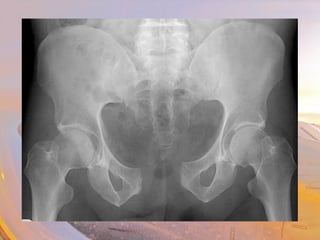

• Femur

• Head

• Inserts into pelvic bone

• Neck

• Most common site of Fx

• Greater trocanter

• Lesser trocanter

• Shaft